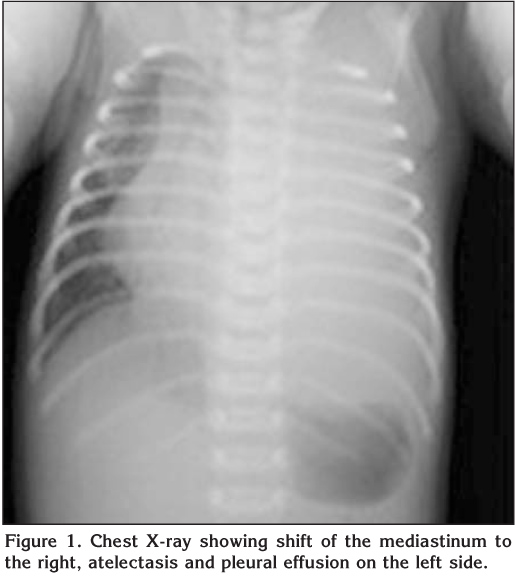

At follow-up, patient's respiratory distress gradually improved. Chest tube was removed on the sixth day of the treatment. Repeated chest X-ray showed that effusion disappeared (Figure 2). However, two days later, the patient's condition deteriorated. He had fever (38.2 ?C) and severe respiratory distress. Laboratory analyses showed leucocytosis (21.500/mm3) with neutrophilia (76%), and increase in serum CRP (138 mg/L). Large left sided pleural effusion was noted on the control chest X-ray. Thoracic ultrasonography showed pleural effusion not exceeding 20 mm in depth. Chest tube was re-placed. Antibiotic treatment was changed to meropenem and clindamycin with suspect of invasive GAS infection. Blood and pleural fluid cultures were taken after the third day of antibiotic revision were negative.? On the 4th day of the chest tube insertion, the patient's condition was well. Both chest X-ray and thoracic ultrasound confirmed decreased pleural effusion on the left lung, so chest tube was removed.? Antibiotic treatment was given for four weeks. The patient was discharged home after full recovery.? By three months of age, his physical and neuro-developmental examination were evaluated as normal.

Figure 2

Chest X-ray and ultrasound are helpful both in the diagnosis of pleural effusion and for monitoring the course of parapneumonic effusion. Pleural fluid culture is an important diagnostic tool leading to identification of the bacterial pathogen in 60-80% of cases, in contrast to blood culture, which is positive in 13-31% (5). In our patient, chest X-ray and ultrasound showed the existence or clearance of pleural effusion and guided us in chest drain management. GAS was isolated from blood and pleural fluid culture of the patient.